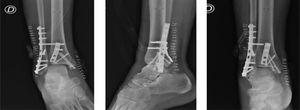

Se indica inicialmente descarga por 5 semanas, luego kinesiología trisemanal con énfasis en movilizaciones y progresando hacia ejercicios de fortalecimiento y reeducación funcional. Sin embargo, la paciente evoluciona con una rehabilitación lenta, tórpida y persiste con dolor y edema intermitente en el tobillo. Por esto, a 11 meses de la lesión inicial, se procede a realizar inicialmente una artrodesis de la sindesmosis tibiofibular. En vista de la mala evolución clínica y radiográfica de la paciente, a los 3 años de evolución se realiza artrodesis tibiotalar con placas (figura 3).